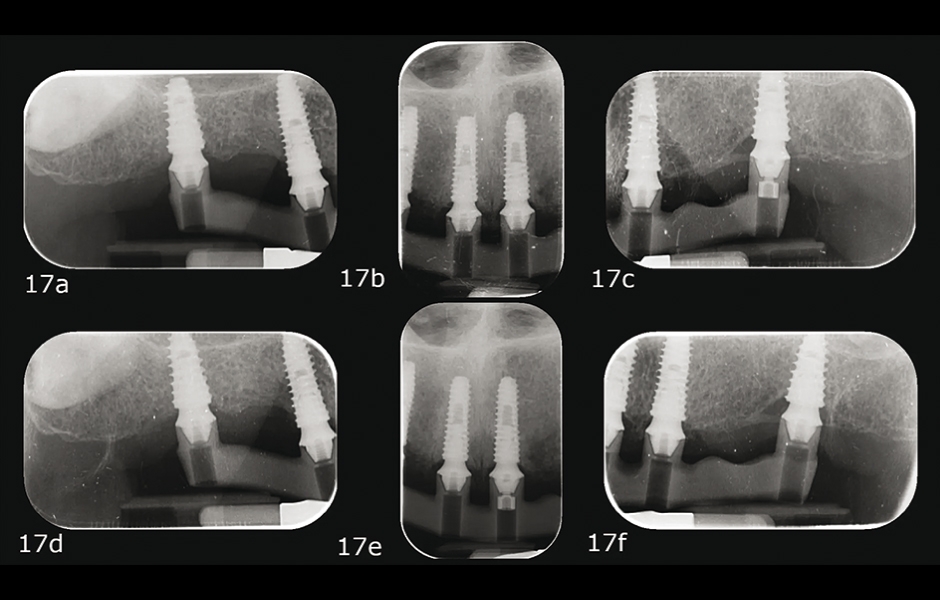

Při druhé návštěvě byl testován PMMA prototyp vyztužený kovovou lištou pro ověření estetické a funkční přesnosti. Pasivní dosed kovové konstrukce byl posouzen pomocí one-screw (Sheffield) testu a taktilní verifikací sondou (obr. 15–17a–f). [15, 16]

Obr. 17a–f: Kontrolní rentgenové snímky během one-screw testu.